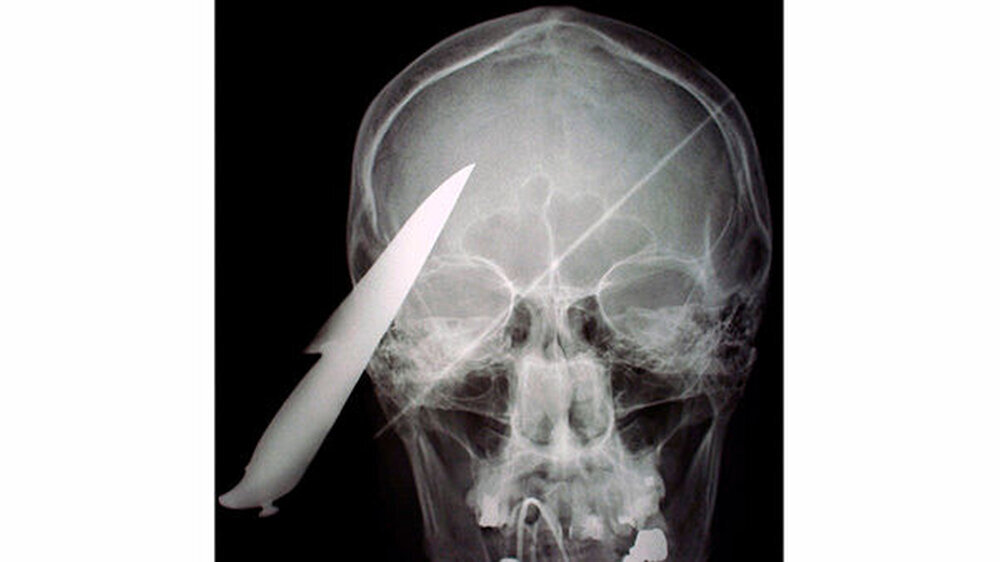

Vom Bohrer im Kopf bis zum Schlüssel in der Kieferhöhle: Die MKG-Chirurgen der Charité haben ausgewählte Patientenfälle mit Fremdkörpern im Gesicht zusammengestellt. In unserer Fotostrecke finden Sie die eindrucksvollen Aufnahmen.